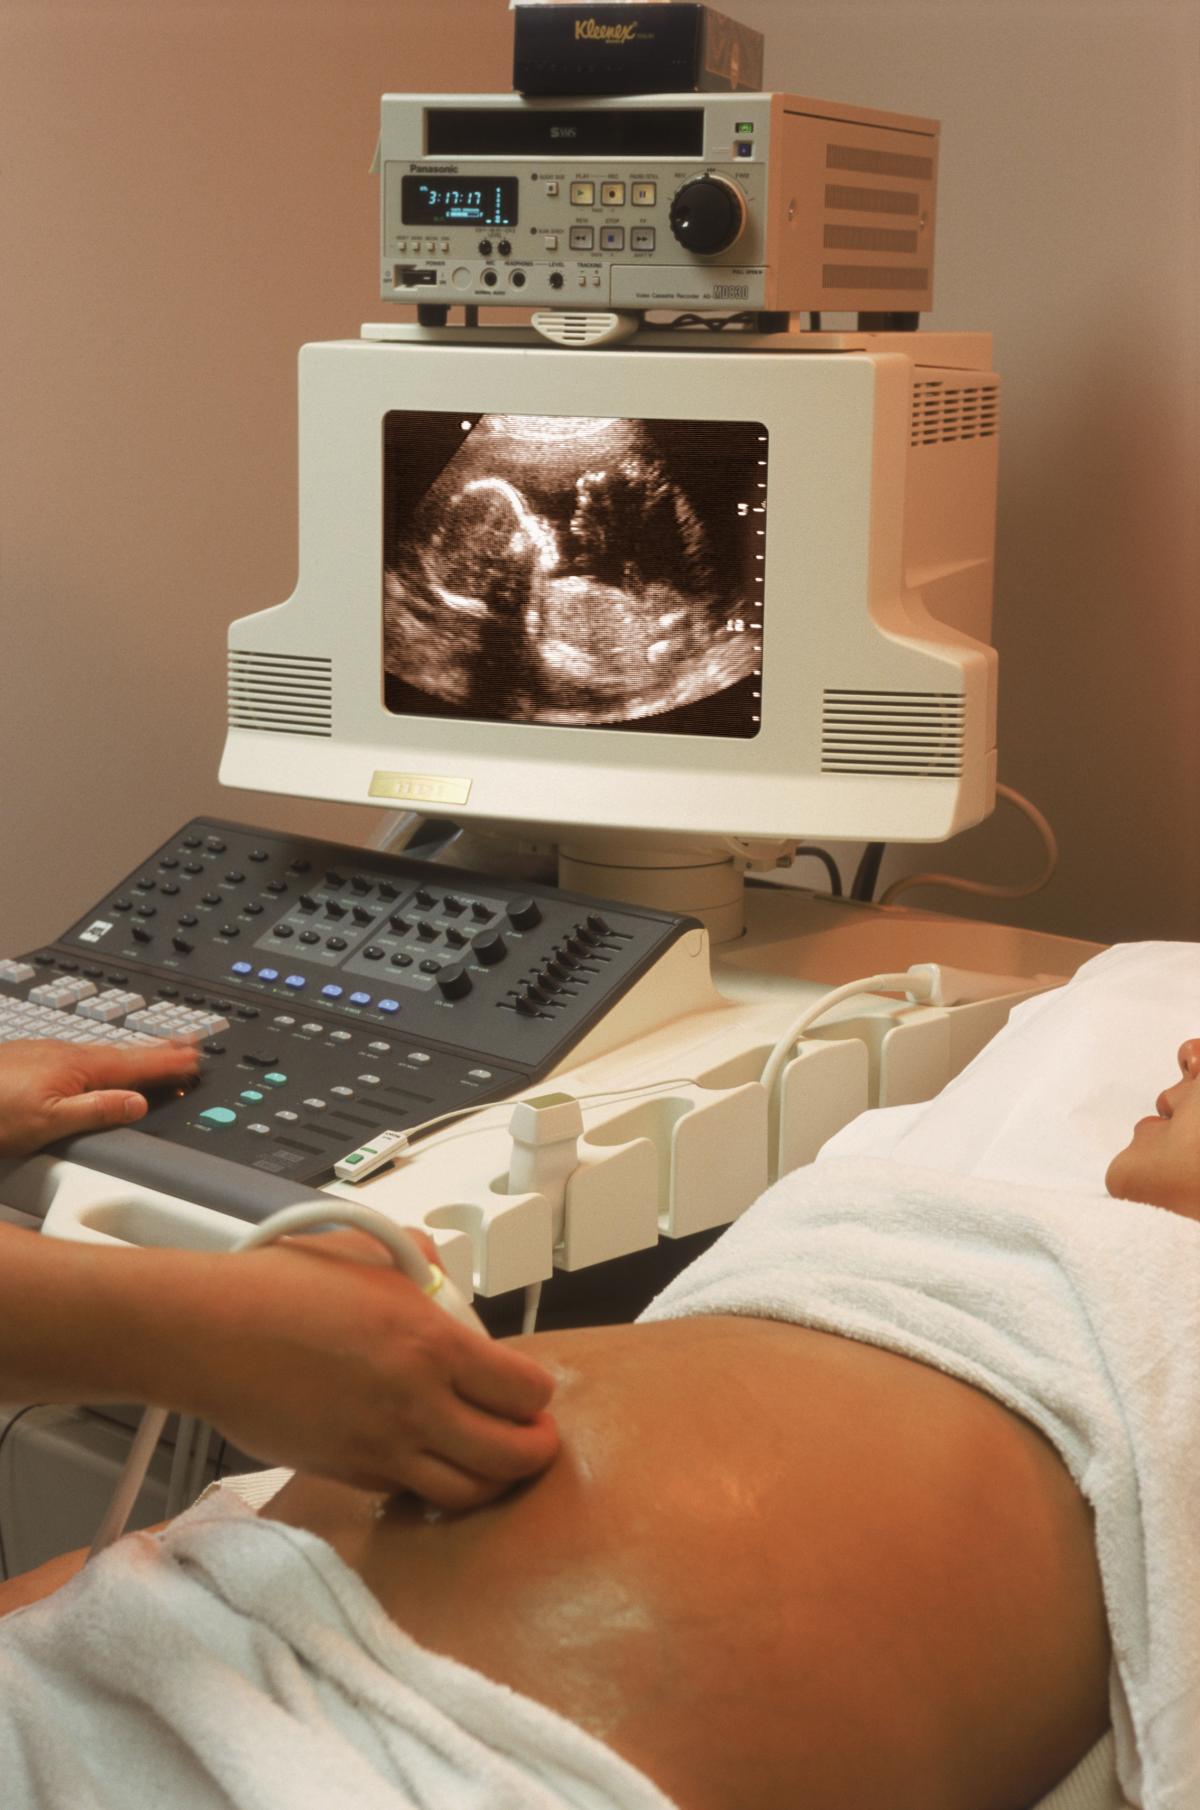

Michelle Hui este una din cele mai norocoase femei după ce și-a văzut visul cu ochii, în ciuda tuturor lucrurilor. Hui a descoperit că, după avortul spontan avut și medicamentele prescrise pentru curățarea uterului de fătul mort, era încă însărcinată!

După șase săptămâni de sarcină, Michelle s-a trezit într-o baie de sânge. Cel mai probabil risca să-și piardă copilul, dacă nu o făcuse deja. După cinci scanări la spital, doctorii i-au confirmat vestea teribilă - suferise un avort spontan. Tot ceea ce rămânea acum de făcut era să-i curețe uterul cu medicamente.

Alte consultări ginecologice au scos la iveală că viața ei era în pericol din cauza unor cheaguri de sânge în uter. Medicii erau nevoiți să intervină chirurgical pentru a salva viața femeii. Numai că atunci când se afla pe masă, aceștia au auzit un sunet imposibil - bătaia unei inimioare. Era vorba de un bebeluș; Michelle era ÎNCĂ însărcinată! Se pare că femeia avusese gemeni și numai unul dintre copii murise.

Medicii le-au explicat cum cheagurile de sânge au acoperit, probabil, fătul în scanările făcute. Familiei i s-a spus că un astfel de caz apare foarte rar și merită propriul loc în jurnalele medicale.